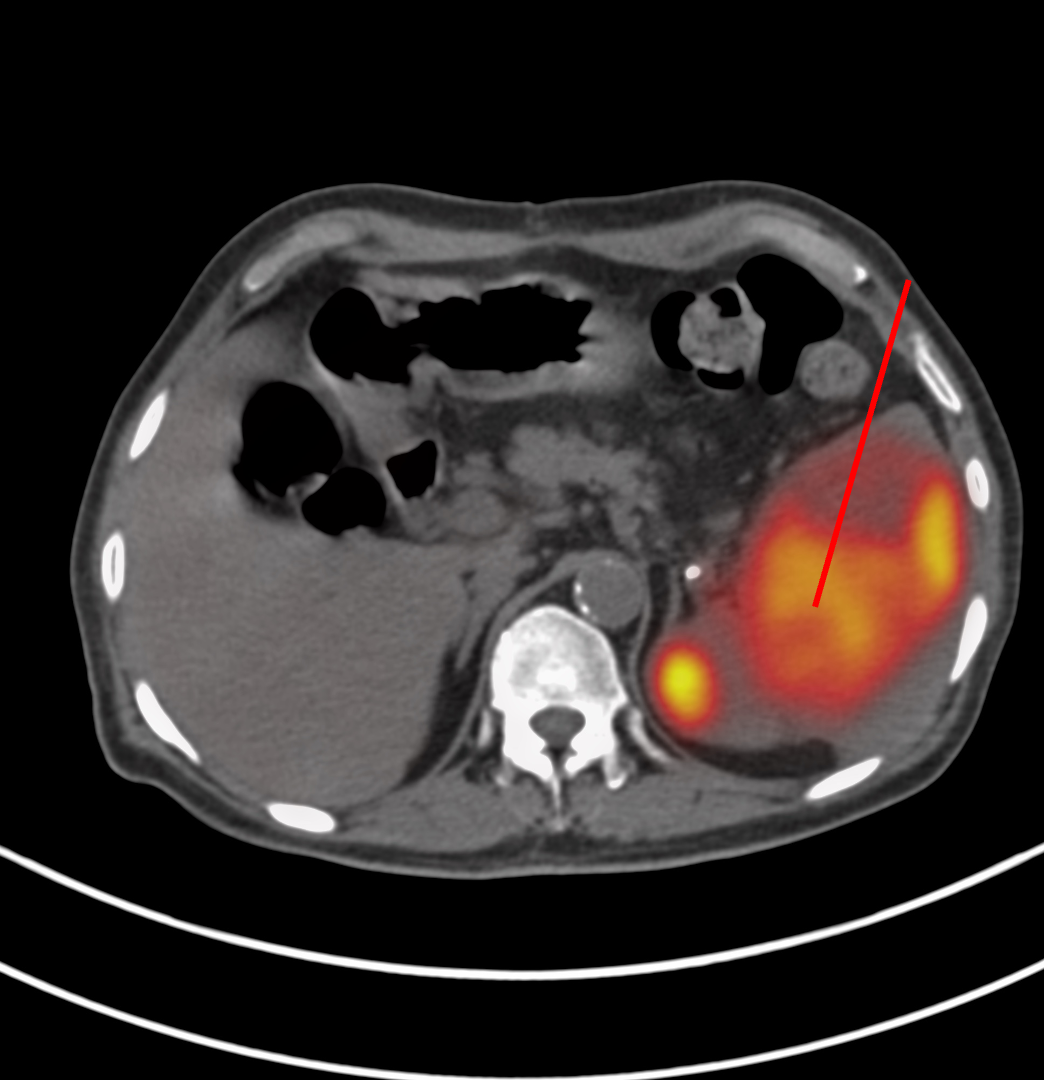

66-years old man presented with a mass in the spleen involving the tail of the pancreas.

The patient came for a biopsy and I decided to use an anterior approach in the supine position.